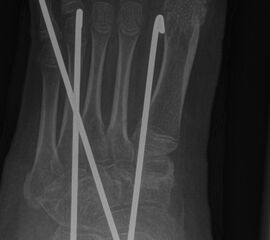

Zusätzlich schränken Wachstumsfugen die Wahl der Osteosynthese ein. Eine die Fuge kreuzende Osteosynthese ist ausschließlich mit Kirschner-Drähten möglich (Abb. 3).

Abb. 3 a-j: Beispiel einer Calcaneusverschiebeosteotomie mit offenen Wachstumsfugen und der entsprechenden Osteosynthese mit Kirschner Drähten. Lokalisation der Osteotomie (a), Lage der Fräse (b-d), Drahtlage mehrere Ansichten (e-h), Heilung der Osteotomie 4 Wochen postoperativ und Entfernung der Drähte (i-j).

Calcaneus-Osteotomie

Die minimalinvasive Calcaneusverschiebeosteotomie bietet eindeutige Vorteile gegenüber dem offenen Verfahren, sodass wir bei Kindern und Jugendlichen nahezu keine offene Verschiebeosteotomie mehr durchführen. Am Calcaneus liegt die offene Wachstumsfuge dorsal. Bei der Durchführung müssen Schenkel der V-förmigen Osteotomie daher etwas steiler angelegt werden, in einem stumpfen Winkel (siehe Abb. 3 a-j). Für die Osteotomie liegen unsere Patienten auf dem Rücken und der BV wird für die exakte Seitaufnahme eingestellt. Der Fuß lagert auf einem hohen OP-Kissen und die Osteotomie kann bequem mit einem langen Kirschner-Draht und einem sterilen Stift angezeichnet werden (Abb. 15).